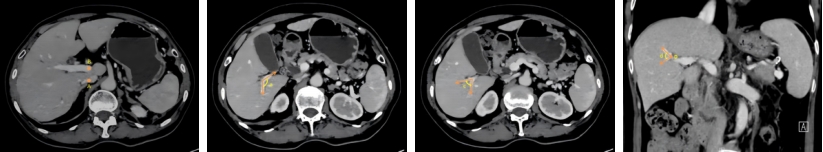

图3 A、B、C、D点及a、b、c、d角在肝脏CT中的位置显示Fig.3 Localization of points A, B, C, and D and angles a, b, c, and d on liver CT images